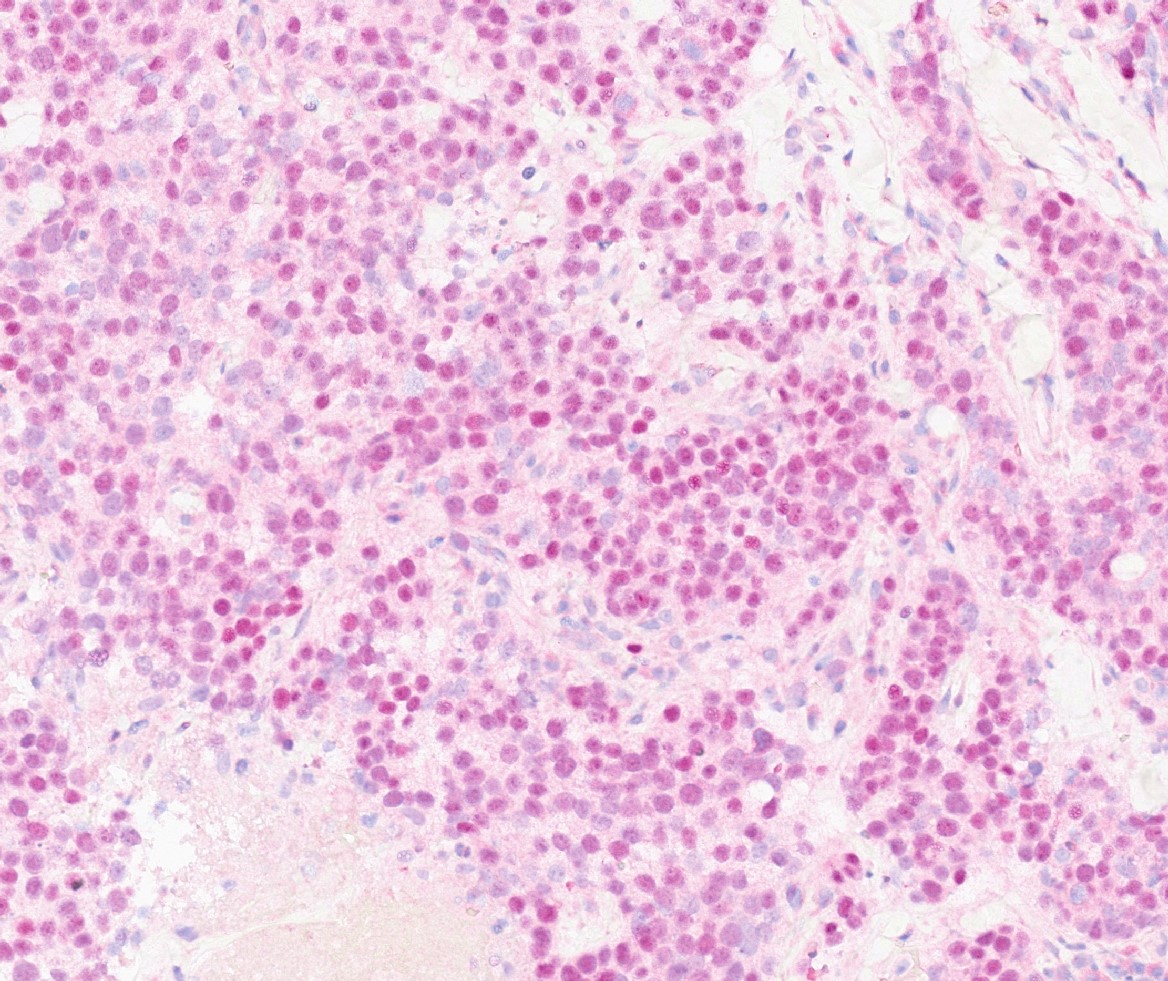

Microscopic (histologic) images

Contributed by Julie M. Jorns, M.D., Kristen E. Muller, D.O., Gary Tozbikian, M.D. and Emad Rakha, M.D.

Positive stains

- Luminal low molecular weight cytokeratins (CK8 / 18, CK19 and CK7 and pancytokeratins such as AE1 / AE3, CAM 5.2, MNF-116), EMA, E-cadherin, p120, ER (60 - 80%), PR (50 - 70%), HER2 (15 - 20%) (Am J Clin Pathol 2006;125:377)

- GATA3 (~91 - 100% of hormone receptor positive breast cancers, ~43 - 66% in triple negative breast cancer) (Hum Pathol 2014;45:2225, Hum Pathol 2015;46:1829)

- TRPS1 (Mod Pathol 2021;34:710)